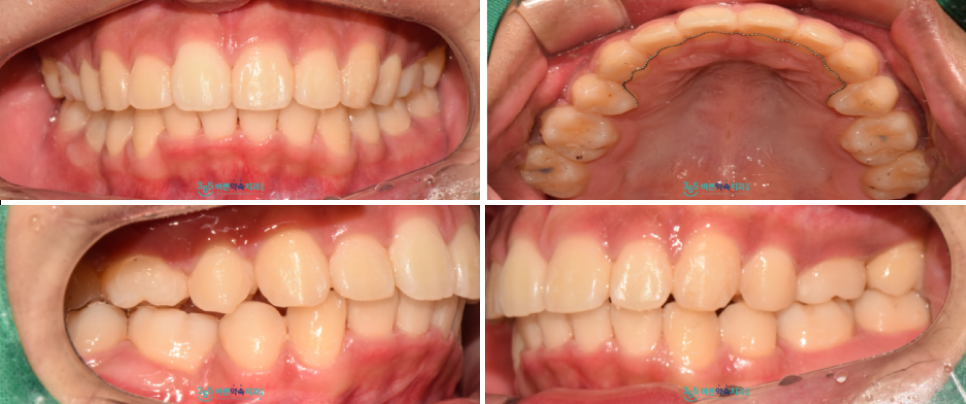

돌출입 교정 치료가

마무리된 구강 내 사진인데요.

환자분께서는 웃는 모습이

훨씬 더 자연스러워지고 좋아지셨다며

만족해하셨습니다.

이렇게 소구치 발치 후

교정치료를 통해

돌출입을 해결해 드린 사례를

소개해 드렸는데요.